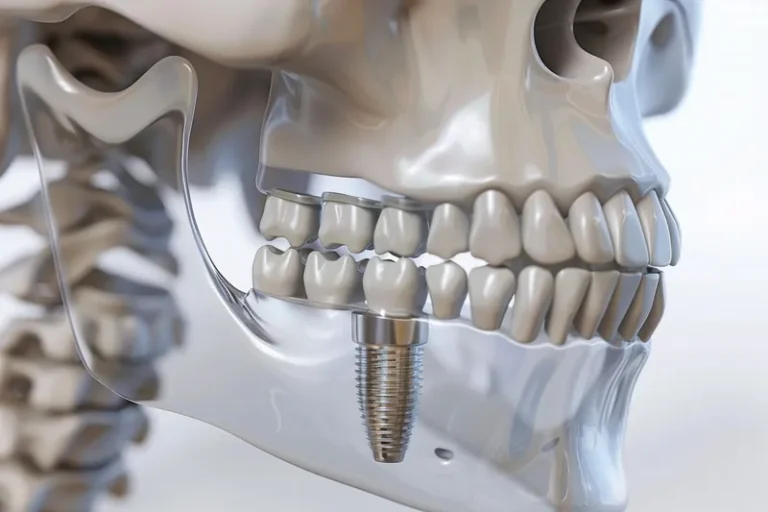

Las diferencias entre implante dental y puente dental son fundamentales para elegir el tratamiento más adecuado. El implante dental consiste en un tornillo de titanio que se inserta en el hueso maxilar, reemplazando la raíz del diente perdido, mientras que el puente dental se apoya en los dientes adyacentes para sostener la prótesis. Aunque ambas…

La regeneración ósea es un procedimiento quirúrgico fundamental en implantología dental que permite recuperar el volumen y la densidad del hueso maxilar o mandibular cuando este se ha perdido. Este tratamiento se vuelve necesario cuando el paciente no dispone de suficiente tejido óseo para sostener un implante dental de manera segura y estable. Mediante el…

Los implantes dentales y los dientes naturales presentan características únicas que los diferencian tanto en estructura como en funcionamiento. Mientras los dientes naturales cuentan con ligamentos periodontales que proporcionan sensibilidad y capacidad de adaptación, los implantes se integran directamente al hueso mediante oseointegración. Esta distinción fundamental influye en aspectos como la sensibilidad a la temperatura,…

La osteointegración es el proceso biológico fundamental que determina el éxito de los implantes dentales. Durante este fenómeno, el hueso del maxilar crece y se fusiona directamente con la superficie del implante de titanio, creando una conexión estructural y funcional que garantiza la estabilidad a largo plazo. Este proceso, descubierto por el profesor Per-Ingvar Brånemark…